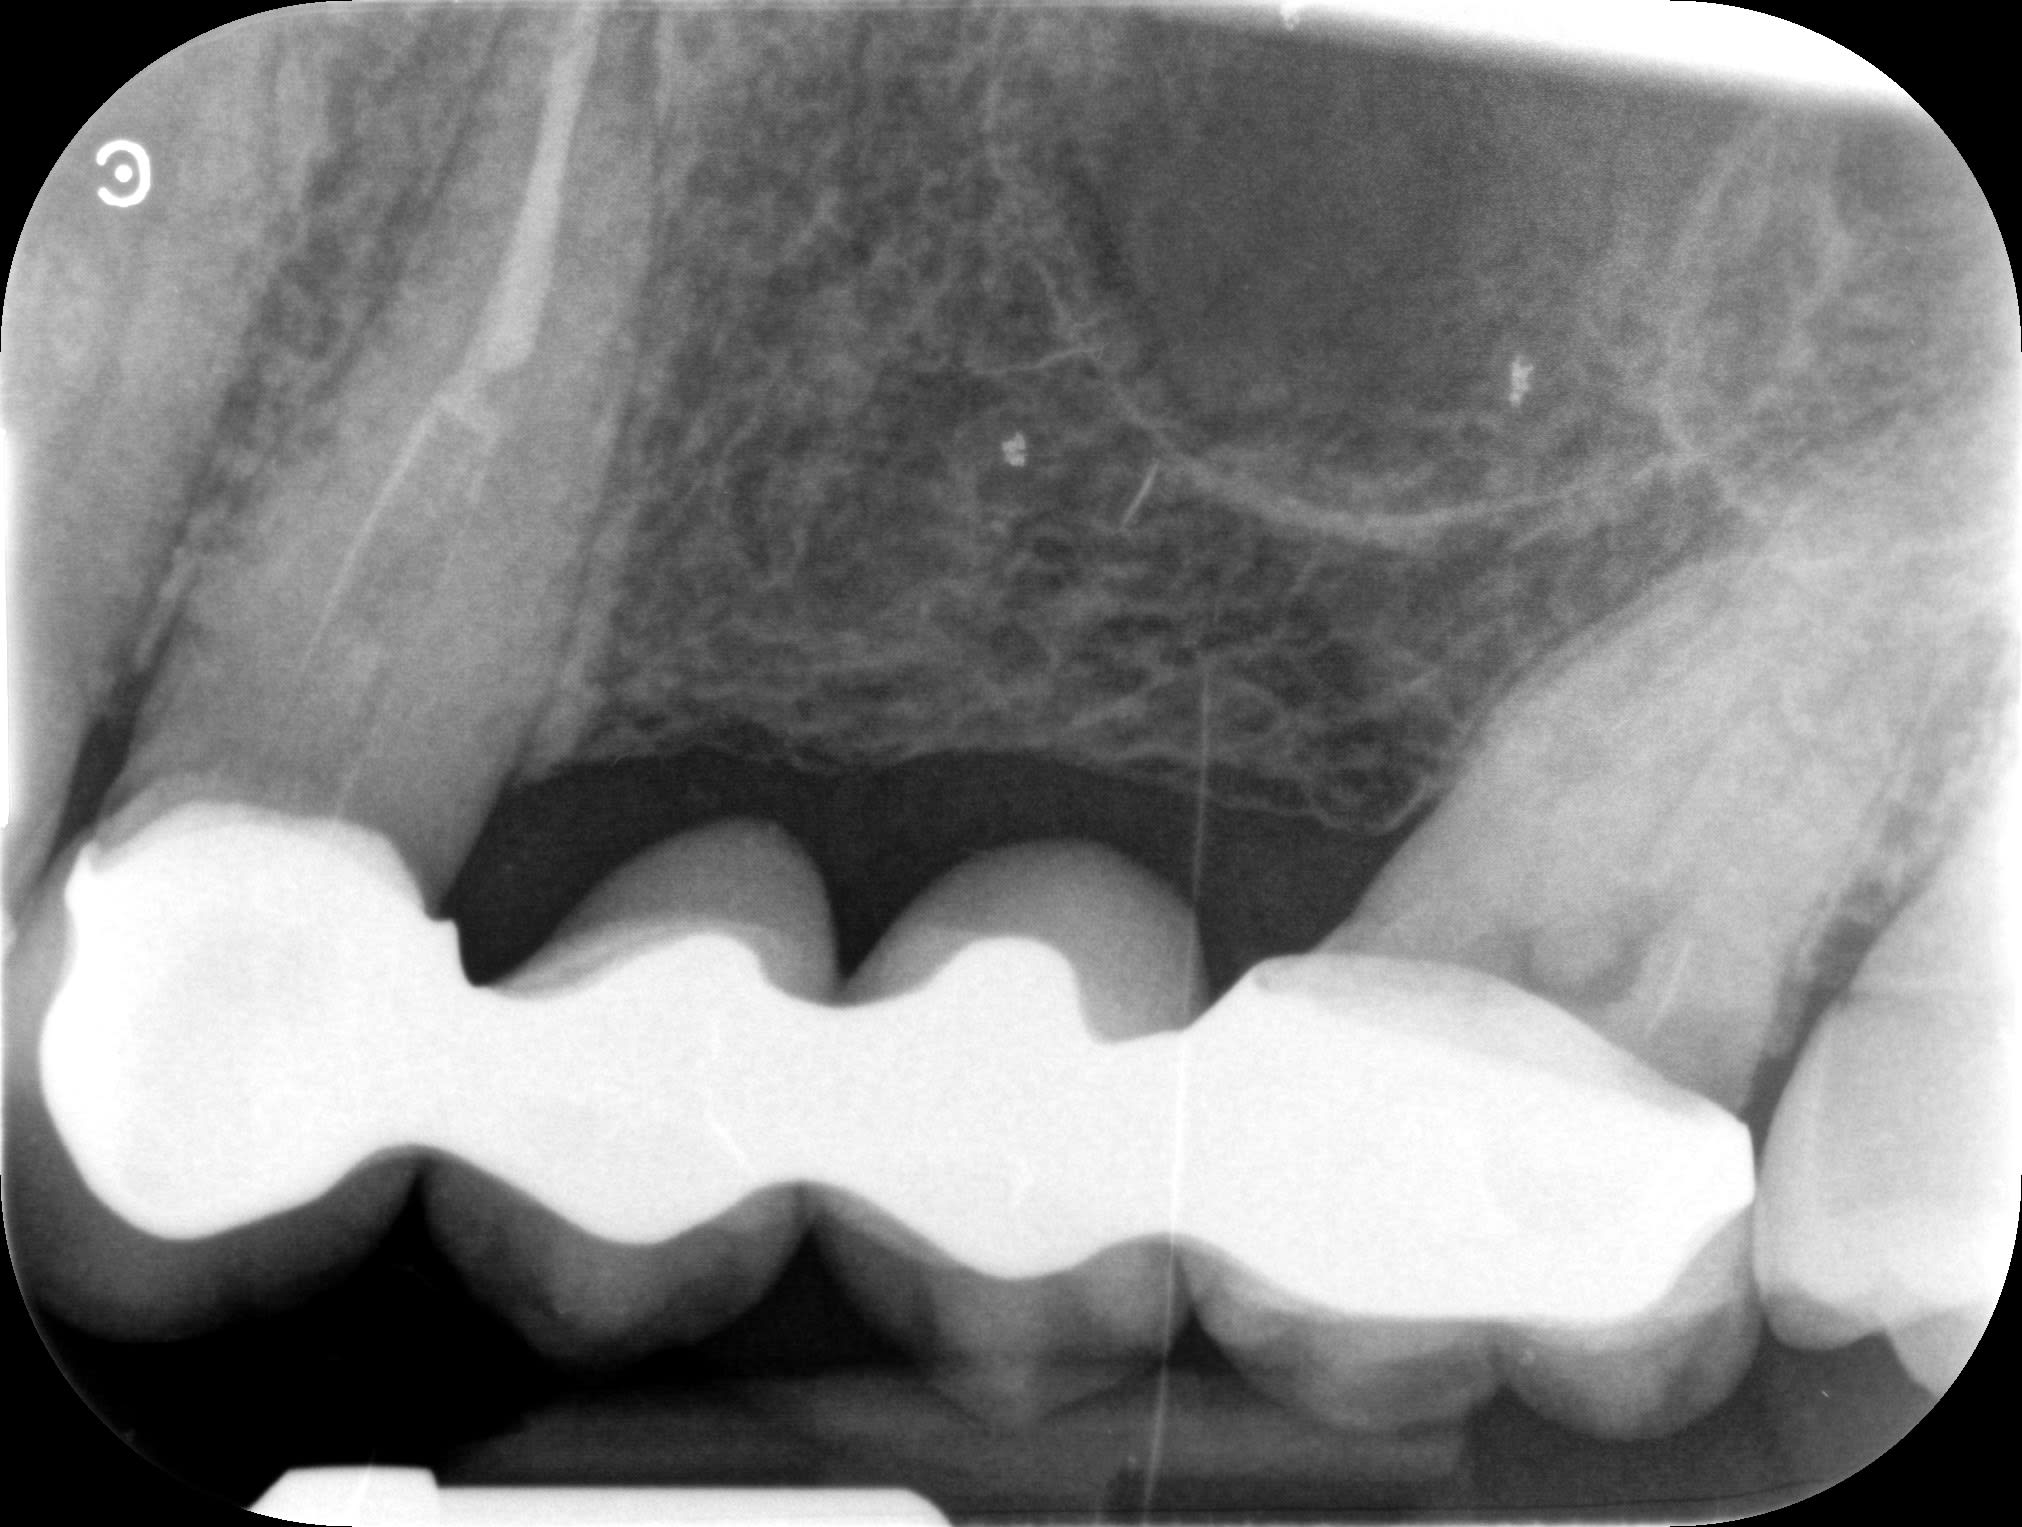

Ce viaduc, j'ai du le faire en 2008. depuis j'ai implanté secteur 4 et anterieur sup, mais il était toujours là en 2019...

Si ça peut te servir...